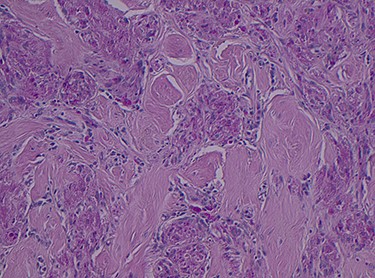

Histopathology of the right hemicolon found five firm nodules in the caecum and an additional seven polyps in the ascending colon macroscopically. Microscopically, a total of eight lesions in the caecum and ascending colon were found to be GCTs, varying in size from 1 to 7 mm. They were submucosal with intact covering mucosa (Figs 1 and 2). Tumour cells had periodic acid-Schiff (PAS)-positive granular cytoplasm and small nucleoli (Fig. 3). Immunohistochemical staining was positive for S-100 (Fig. 4) and inhibin. Twenty-four lymph nodes identified showed no abnormality. Spindling was seen in some tumours in this case, but overall, there are less than three worrisome features, and as such, these GCTs were considered atypical. Other polypoid lesions identified included two hyperplastic polyps and a submucosal lipoma.